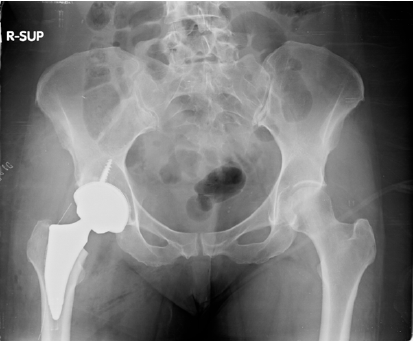

The patient was a female of 58 years old, who had right chronic hip pain (Table 2) due to hip osteoarthritis treated for many years with medicines and intrarticular injections of corticosteroids first and then of hyaluronic acid. In November of 2019 she was scheduled for total hip replacement by her Physicians (M.P, D.L.) and 3 months after she underwent to surgery (primary total hip arthroplasty, Adler Ortho®) (Figure 6). She had an uneventful postoperative period where she started postoperative rehabilitation and she was formally discharged from hospital after four days. She continued her rehabilitation program until the closure of physiotherapy centres due to the general Italian lockdown, on 9 March of 2020. The patient missed several postoperative check-ups because of Covid-19 pandemic. In July 2020 she called her general practitioner for difficulty walking without crutches, even after a short ride, and she was referred to her surgeons. After 5 months, the surgeon noticed a Trendelenburg’s sign positive, probably caused by gluteal muscles weakness with a waddling gate. Now the patient is following a strict home rehabilitation program prescribed by physiatrist to reinforce gluteal muscles (A.A).

Figure 6: Total hip replacement on X-ray postoperative control.